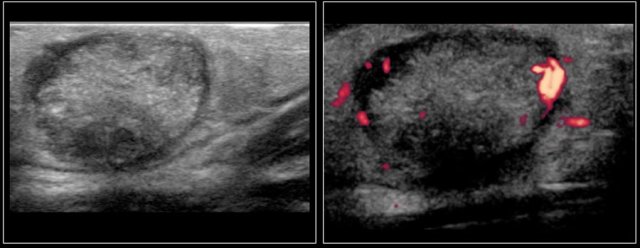

Here we see images of a highly vascular lesion in the left submandibular region, which was present at birth.

Three months later it had decreased in size.

A soft swelling was present on the side of the head in a six-week-old boy.

It was small at birth and showed rapid growth.

This is typical for an infantile hemangioma.

Venous malformation

A six-month-old boy presented with a swelling in the left neck at birth.

Several ultrasound examinations could not differentiate between a hemangioma or a venous malformation.

At six months of age, the ultrasound showed a lesion, which was mostly composed of vessels which increased in size on straining.

On color Doppler the lesion showed increased flow while crying.

The final diagnosis on imaging and on clinical examination was a venous malformation.